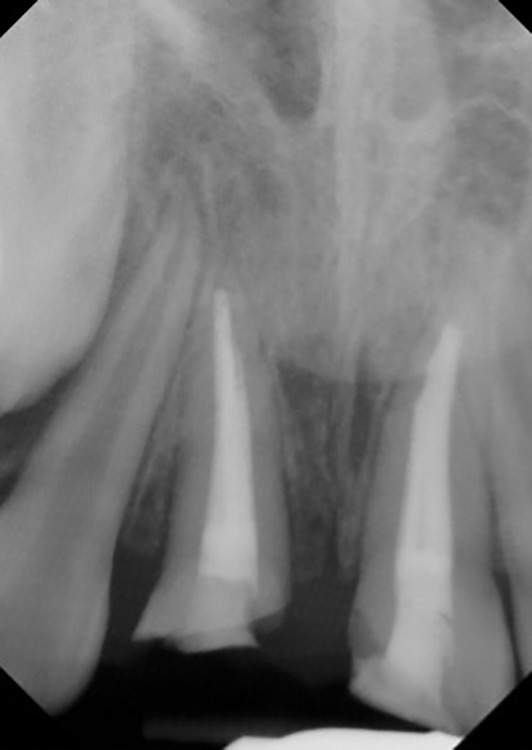

Aim: This case report discusses an 11-year-old patient who experienced intrusive luxation of the anterior teeth due to trauma. The condition was treated with nonsurgical root canal treatment (NS-ReTx) followed by decoronation.

Background: Intrusive luxation, a prevalent dental injury in children, necessitates prompt intervention. Nonsurgical root canal treatment, a conservative approach, is frequently employed. Decoronation, which involves the removal of the damaged tooth structure, is crucial for access and cleaning. This procedure, followed by restorative care, can help preserve the tooth and prevent future complications.

Case description: An 11-year-old male patient with luxative intrusion of teeth 11 and 21 was treated conservatively with nonsurgical root canal therapy, followed by the decoronation of tooth 11.